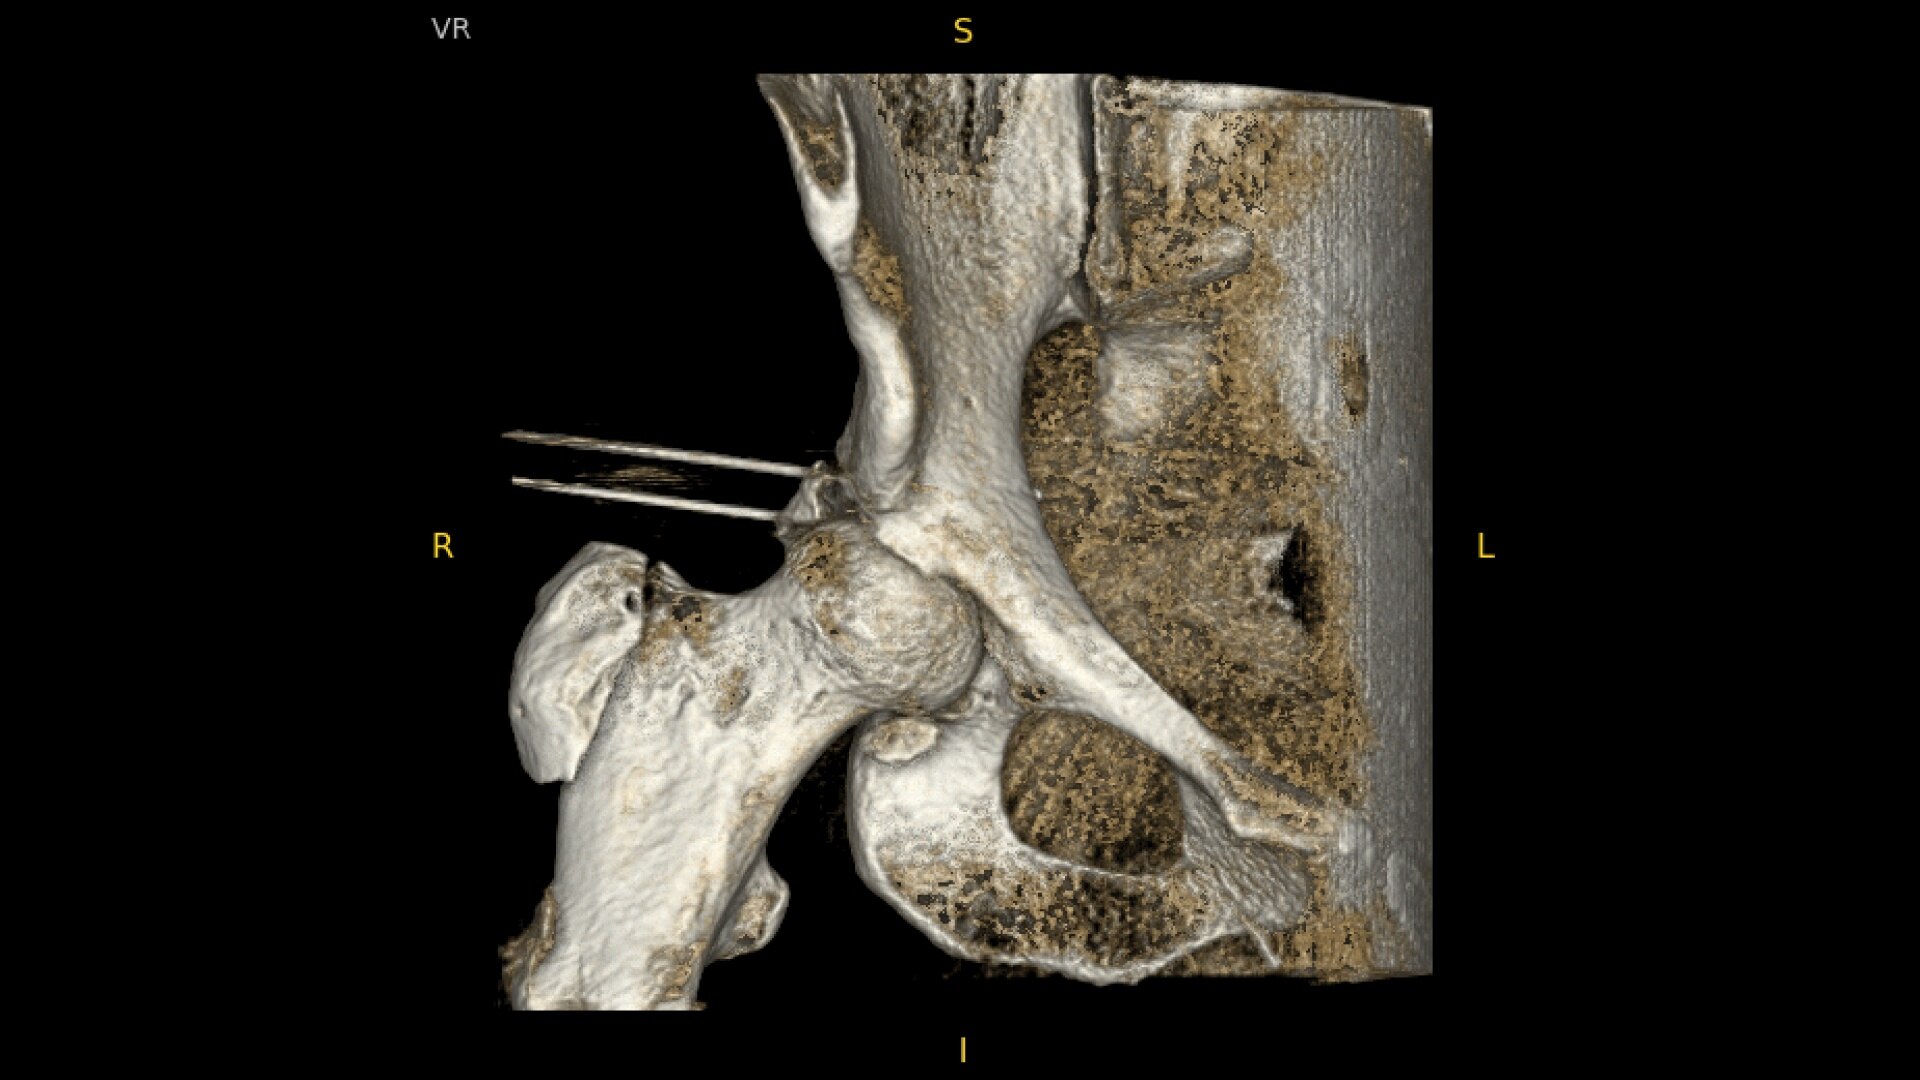

OEC C-arms provide orthopedic imaging with a large field of view optimized to clearly visualize orthopedic anatomy, such as the entire long bone femur or minute fractures in extremities. A clear display with comfortable viewing can easily show AP and lateral views, enabling efficient procedure planning.

Live Zoom up to 4X during a fluoro without the additional dose of Mag modes to assess orthopedic fractures and fixations.

See precise anatomical detail of varying densities such as bone and soft tissue with a high dynamic range with the OEC Elite CFD with a flat detector, image processing advancements and 4K viewing display.

Complex orthopedic procedures require powerful imaging systems. OEC premium C-arms perform in a variety of procedures such as:

• Hip fracture fixation

• Hip replacement